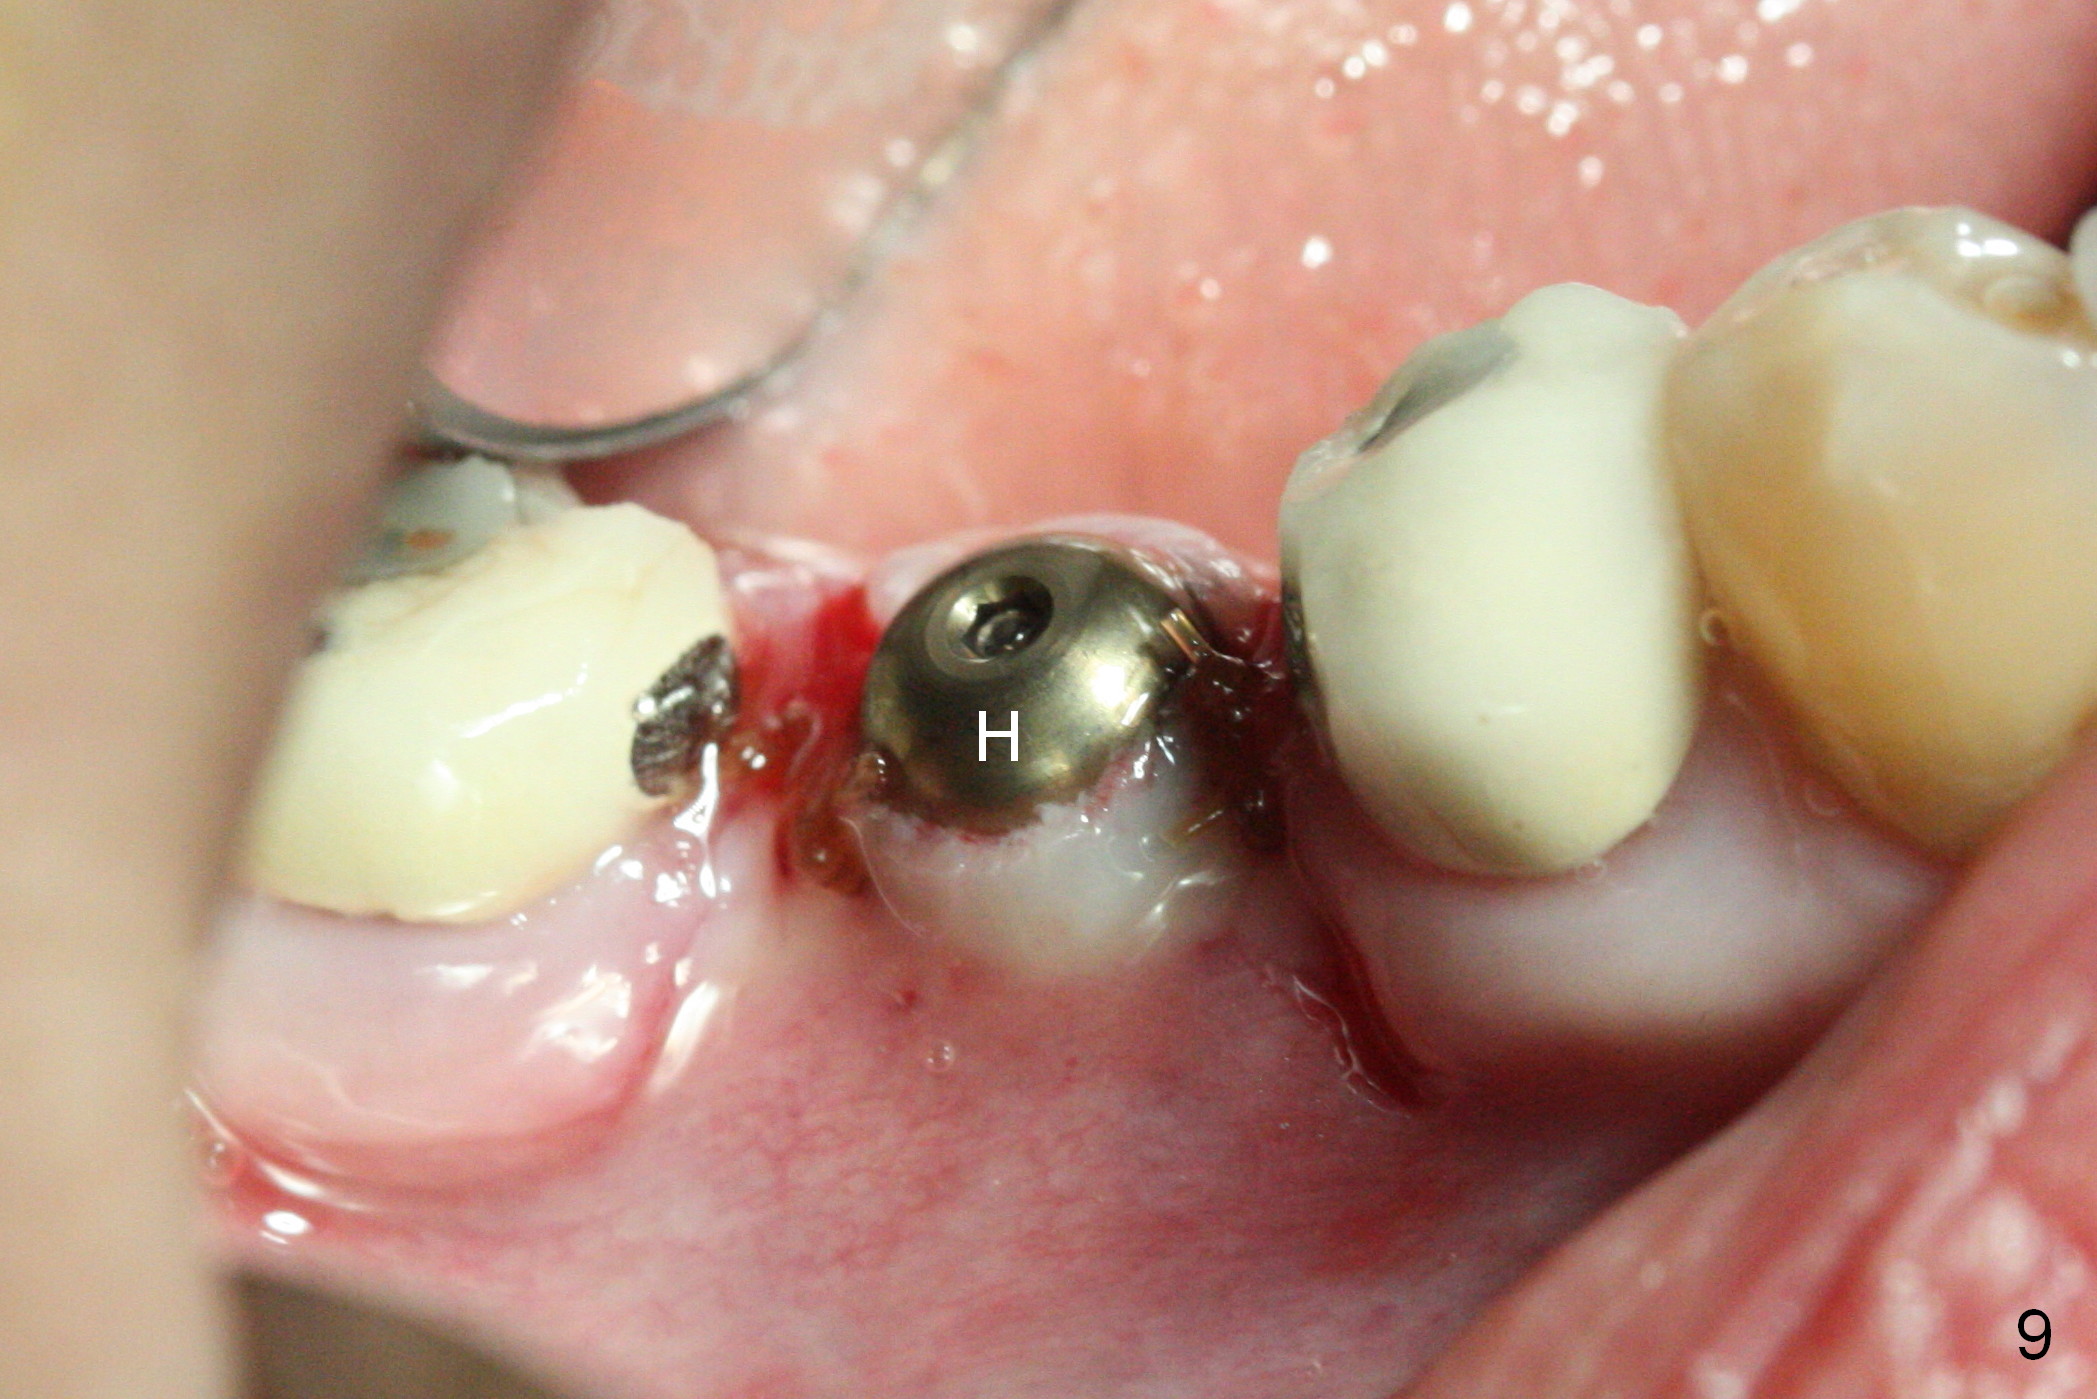

CBCT was taken (Fig.1,2 (P: pontic; S; submandibular fossa)) several months prior to #29 and 31 RCT and #31 porcelain chip (Fig.3). When the bridge is sectioned, the pointed ridge at #30 (Fig.1) is confirmed (Fig.4,5). After flattening the ridge until 6 mm buccolingually (Fig.6 arrowheads), osteotomy is initiated with 1.6 mm drill at 9 mm; there is 2.5 mm clearance from the superior border of the Inferior Alveolar Canal (red dashed line). A 4.5x9(1) mm Magicore is placed with 35 Ncm (insertion torque) after 4.3 mm Magic Drill; a 4.5 mm healing abutment (Fig.7 H). An error occurs because of using 1 mm cuff of the Magicore. Ideally 3 or 4 mm cuff should have been used because of reduction of the ridge by ~ 3 mm (Fig.2). The result of the error is failure of placing the implant at the desirable depth (<9 mm). The coronal threads are exposed and have to be covered by bone graft (autogenous bone and allograft (.5-1.5 mm) (Fig.8 *), followed by collagen dressing. Extra suturing is done to securely close the wound (Fig.9), followed by periodontal dressing (data not shown).

The wound is healing 8 days postop (Fig.10). Because of the short cuff (subgingival margin), screw retention type of restoration will be used, in contrast to cement type of the 2nd case. In fact, FC one is used.